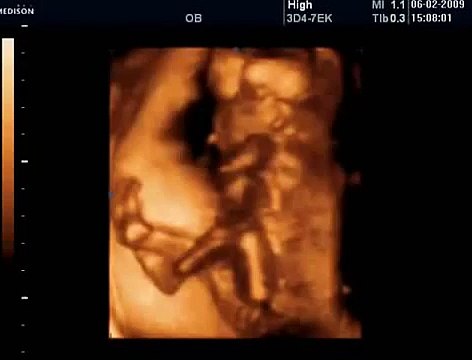

33 Haftalık Gebelik Bebek Ultrason Görüntüsü

Hafta hafta gebelik dönemi 33 haftalık bebek ultrason görüntüsü. Gebelikte 33. hafta daha çok bilgi için gebelikveannelik.com/33-hafta-gebelik sayfamızı ziyaret edebilirsiniz.